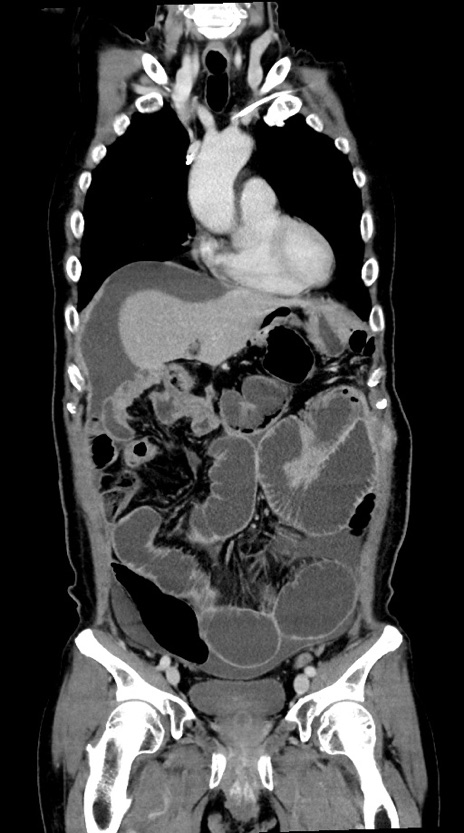

症例28(冠状断像)

【症例】60歳代男性

【主訴】嘔吐

【現病歴】胃癌にて胃全摘後。食思不振が悪化し、夜中に嘔吐することがある。

【既往歴】胃癌、胃全摘、脾摘、胆摘後

【データ】WBC 5900、CRP 10.56